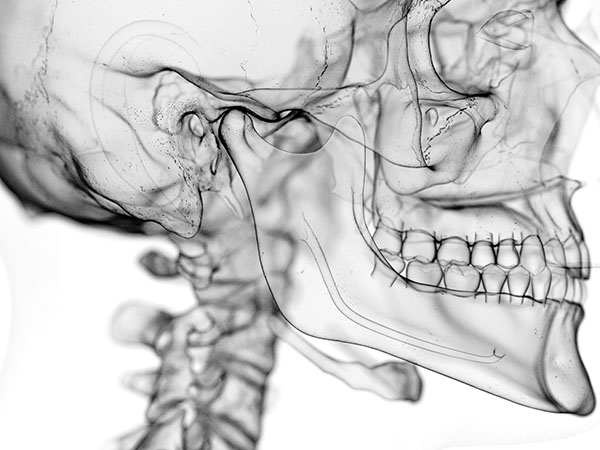

사랑니가 신경과 맞닿아 있는 상황을 제외하고는 안전하고 신속하게 발치가 가능합니다.

사랑니가 비스듬하게 누워있는 경우에는 수술적인 방법을 통해 발치를 해야 하며 신경과 맞닿아 있는 경우에는 사랑니 발치 시 신경손상의 우려가 있음으로 주의하셔야 합니다.

사랑니 뿌리근처에는 아래턱 신경이라는 커다란 신경이 지나갑니다. 개개인마다 다르지만 뽑는 과정에서 신경에 손상을 일으킬 가능성이 있습니다. 신경손상 가능성에 대한 사전 분석이 필요하며 손상가능성이 있다고 판단되는 경우 경험 많은 의사에게 조심스러운 발치 및 후처리가 요구됩니다.